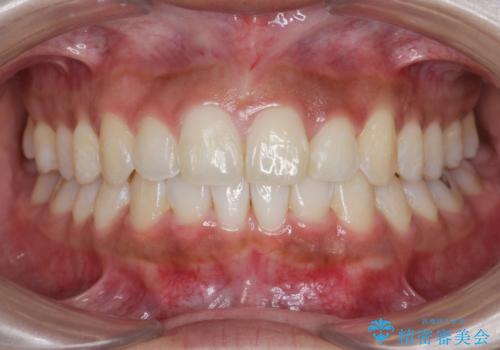

- 前歯のガタつき、突出感のある前歯の改善を求めて来院されました。

前歯の角度を改善し審美性を高めるとともに、奥歯のガタつきも並べ直すことで安定した咬合関係の確立を目指します。

歯列の側方拡大をしっかりと行ったことで歯を抜かずに前歯の角度をしっかりと改善することができました。